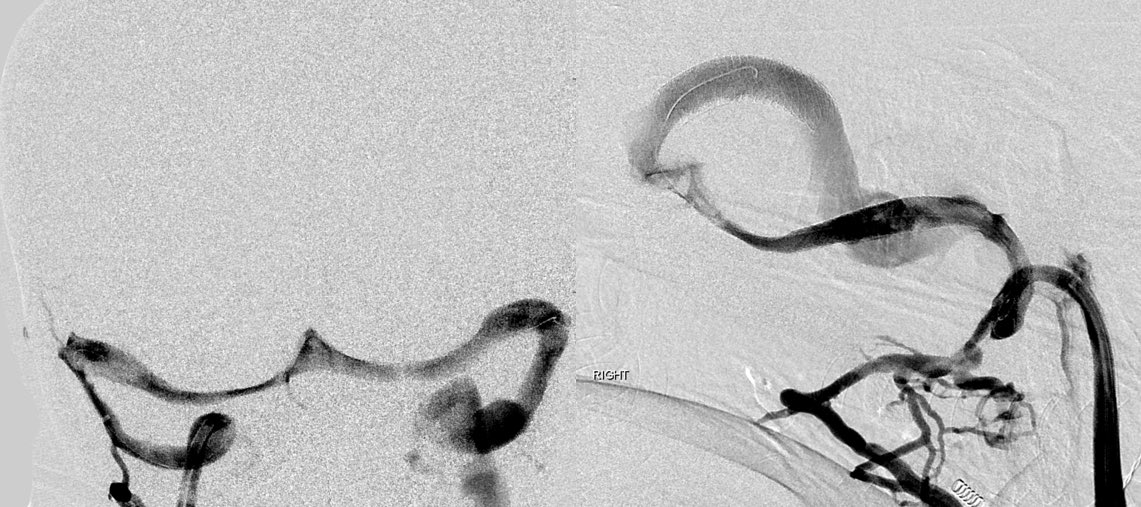

Here is an example of an intracranial venogram pre and post stenting of the b/l Transverse/sigmoid sinus junctions